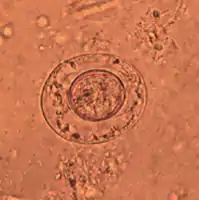

Image reveals ultrastructural details of a single Hymenolepis nana tapeworm ovum

An egg of dwarf tapeworm

As its name implies (Ancient Greek: νᾶνος, nānos – dwarf), it is a small species, seldom exceeding 40 mm long and 1 mm wide. The scolex bears a retractable rostellum armed with a single circle of 20 to 30 hooks. The scolex also has four suckers, or a tetrad. The neck is long and slender, and the segments are wider than long. Genital pores are unilateral, and each mature segment contains three testes. After apolysis, gravid segments disintegrate, releasing eggs, which measure 30 to 47 µm in diameter. The oncosphere is covered with a thin, hyaline, outer membrane and an inner, thick membrane with polar thickenings that bear several filaments. The heavy embryophores that give taeniid eggs their characteristic striated appearance are lacking in this and the other families of tapeworms infecting humans. The rostellum remains invaginated in the apex of the organ. Rostellar hooklets are shaped like tuning forks. The neck is long and slender, the region of growth. The strobila starts with short, narrow proglottids, followed with mature ones.